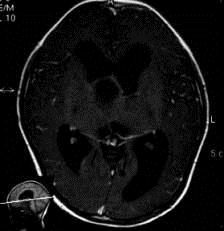

问题 病历摘要:??患者女性,6岁,半年来感觉视力模糊,近10天出现反复头痛,间有恶心呕吐,精神转差,查体:神志清楚,身高90cm,体重25Kg,血压90/55mmHg,右眼视力4.6,左眼视力4.8,双侧视乳头水肿,颈软,伸舌居中,四肢肌张力正常,肌力5级,双侧Babinski征(-)。 患者术后第三天,病情加重,检查生化,血钠145mmol/l,尿比重1.010g/l,复查头部CT,发现右侧大脑中动脉供血区域密度减低,右侧脑室受压,蛛网膜下腔、脑室内少量积血,中线有移位,环池显示欠清,这时应采取的治疗措施有?

选项 A.甘露醇125ml快速静滴 B.尼膜地平静滴舒张血管 C.右侧额颞开颅去骨瓣减压术 D.低分子肝素皮下注射 E.右侧额颞开颅颞叶切除术 F.侧脑室穿刺外引流术 G.右侧额颞开颅去骨瓣+颞叶切除术